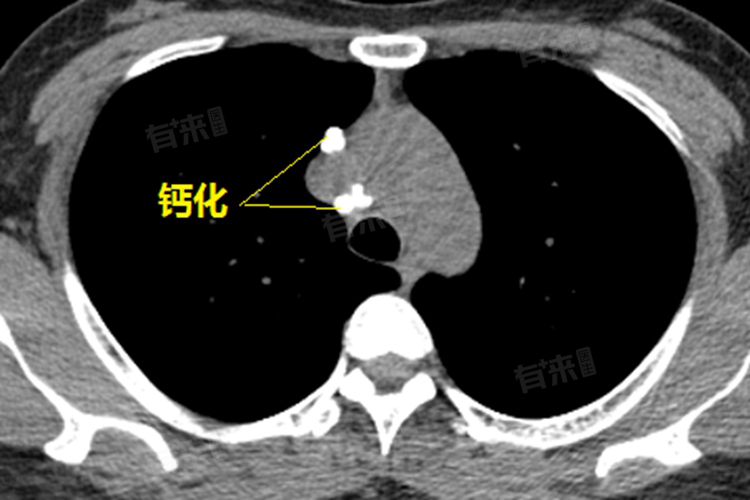

钙化灶一般是由炎症和结核引起,由局部组织中钙盐沉积形成。如肺结核在治愈后可形成肺部钙化灶。但也可能是组织局部坏死后形成的纤维化瘢痕,如肝内钙化灶。临床常见的类型有肺钙化灶、肝钙化灶、前列腺钙化灶、肾钙化灶等。钙化灶还常见于椎间盘钙化症、组织胞浆菌病、类脂质蛋白沉积症、胸壁软组织肿瘤、脑型肺吸虫病、碱性磷酸钙结晶沉积病、颅内海绵状血管瘤等疾病。

钙化灶通常是病灶恢复以后,到了一定时间逐渐愈合,出现了改变局部钙质沉淀的现象。这种情况下,钙化灶的性质比较稳定,不会再出现异常变化,所以并不严重。其相当于局部出现病灶导致的瘢痕一样,对人体的影响非常小。但如果钙化灶较大或 位于特殊位置,可能会对周围组织产生压迫,如压迫神经或血管,从而引起相应的临床症状,如胸憋气紧、局部麻木、排尿异常、颈部不适等。但即便如此,钙化灶相比肿瘤而言,其严重性仍然较低。